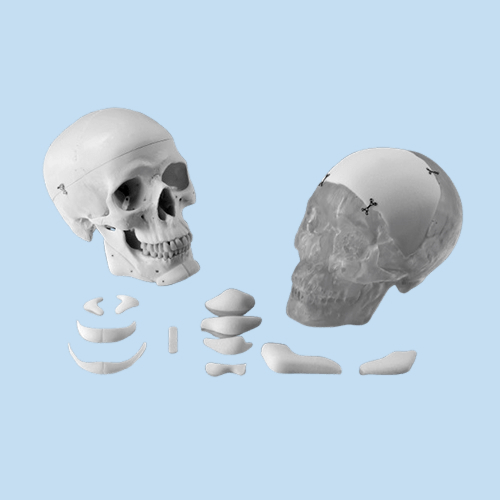

OMNIPORE® de Matrix Surgical es un implante poroso de alta densidad diseñado para reconstrucción cráneo-facial y cirugía estética. Fabricado en polietileno poroso, permite ser fresado, cortado o moldeado durante la cirugía para una adaptación precisa a la anatomía del paciente. Su estructura favorece el crecimiento tisular, promoviendo una mejor integración y estabilidad a largo plazo. Se suministra estéril y listo para su uso inmediato, evitando riesgos de contaminación al no requerir reesterilización.